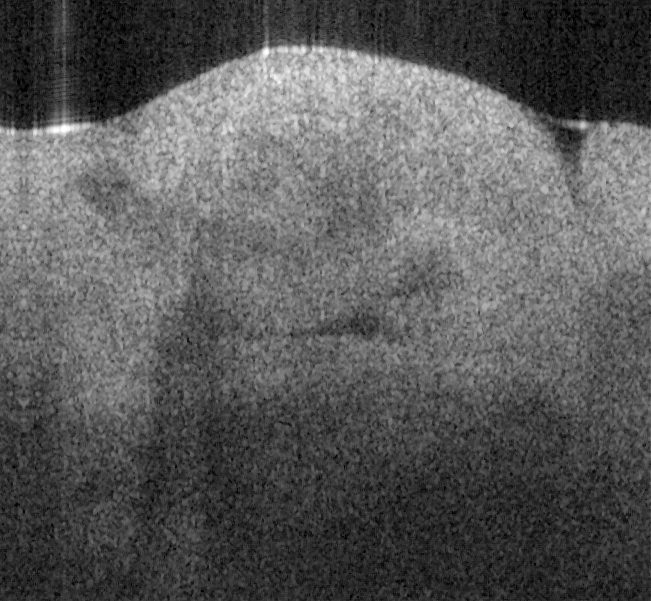

Fig. 17 shows ex vivo images of coronary artery of rabbit with forward-view (a, b) probe with

ball lens #16 and side-view (c, d) probe with GRIN lens #5 acquired by our catheter-based

complex SS-OCT using our 3x3 Mach-Zehnder interferometer with unbalanced differential

detection technique with image size of 2.5x2mm by scanning the probe along the artery (a, c)

and scanning cross the artery (b, d). Three layers of tunica intima, tunica media, and tunica

adventitia for the coronary artery are viewed clearly as indicated by the gray, black, and

white arrows in all four images in Fig. 17. The fine layers of muscle and elastic fiber in the

tunica media of the coronary artery are shown obviously in the images obtained by

scanning the probe cross the artery.

Fig. 17. Ex vivo images of coronary artery of rabbit scanning along the artery (a, c) and

scanning cross the artery (b, d) with forward-view probe (a, b) with ball lens #16 and side-

view (c, d) probe with GRIN lens #5 acquired by our catheter-based complex SS-OCT using

our 3x3 Mach-Zehnder interferometer with unbalanced differential detection technique.